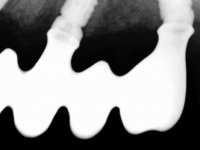

Paciente do sexo masculino, com 64 anos de idade e não fumador. Apresentava uma prótese combinada superior composta por uma ponte metalo-cerâmica fixa de 6 elementos (1.3,1.2,1.1,2.1,2.2, e 2.3) e uma prótese esquelética superior também com 6 elementos. No maxilar inferior apresentava duas pontes metalo-cerâmicas, uma de 3 elementos no 4º quadrante e outra de 2 elementos no 3º quadrante. A adaptação das pontes estava comprometida e esteticamente não satisfaziam o paciente. A higiene oral não era satisfatória.

Realizada uma TAC, foi planificada a colocação de 6 implantes no maxilar superior. Foi decidida a colocação de dois implantes na zona dos incisivos centrais, dois implantes na zona dos caninos e dois na zona dos segundos pré-molares. A ausência de estrutura óssea na zona distal do primeiro quadrante implicava a realização de uma regeneração óssea no seio maxilar direito. A cirurgia foi realizada e após a colocação dos implantes foi feita a impressão para confeção de uma prótese provisória metalo-acrílica aparafusada para colocação em carga imediata no dia seguinte. O implante colocado na zona do seio maxilar direito não foi colocado em carga. Passados 6 meses foi realizada a impressão aos 6 implantes com técnica de moldeira aberta e foram confecionados os modelos de trabalho. Numa consulta seguinte foram montados os modelos de trabalho em articulador semi-ajustável utilizando o arco facial e a relação inter-maxilar obtida com a prótese provisória. Foi feita uma muralha de silicone sobre a ponte provisória com o objetivo de orientar o trabalho laboratorial. Realizada a infra estrutura metálica aparafusada esta foi provada em boca e finalmente após colocação de cerâmica o trabalho foi colocado definitivamente. Como passaram vários meses após a realização da primeira TAC foi feita uma segunda para planificar a colocação de implantes no 4º quadrante. Colocaram-se 3 implantes na mesma sessão em que foi feita a extração dos pilares da ponte. Estes implantes foram posteriormente reabilitados com uma ponte metalo-cerâmica aparafusada de três elementos.